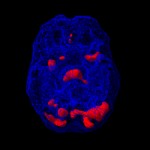

Možganska slika 68 letne ženske, ki so jo zdravili za Alzheimerjevo boleznijo. Predvidevali so da gre za ta tip demence zaradi simptomov, ki jih je imela – pogosto je pozabila imena svojih otrok, vnukov, se izgubila…Ampak možganska slika je pokazala normalno aktivnost v frontalnih in temporalnih predelih, kar ni značilno za Alzheimerjevo bolezen. Edina nepravilnost v možganih je bila prevelika možganska aktivnost v limbičnem sistemu, kar je značilnost ljudi, ki trpijo za depresijo. Šele tako je lahko dobila pravilna zdravila, ki so zmanjšala simptome njene bolezni.